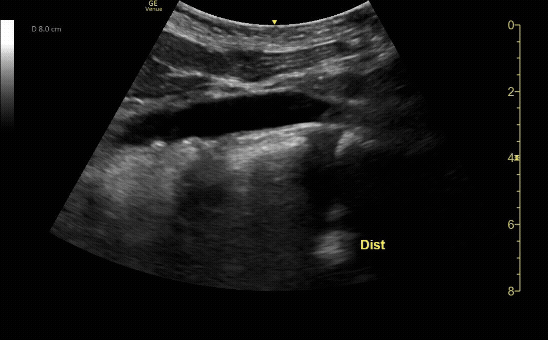

Distal transverse (short) view demonstrating the bifurcation. Measure anterior-to-posterior proximally. Should measure <3cm and taper distally.

c/o Taylor Wahrenbrock, MD